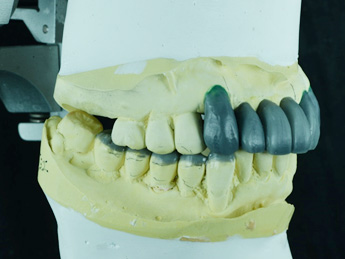

診断用ワックスアップです。

プロビジョナルレストレーションに置き換え、適正な咬み合わせに調整していまます。